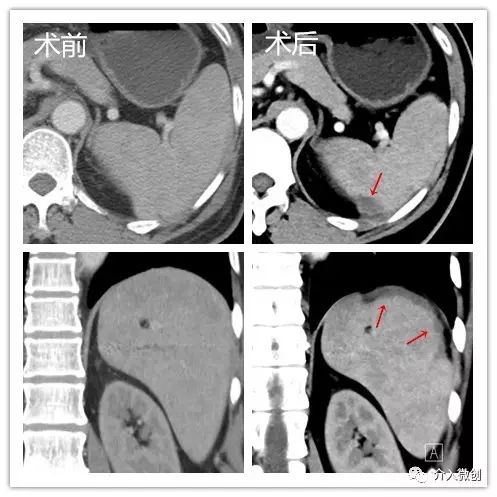

- 术后复查CT显示脾脏部分梗死。

术后复查CT显示脾脏部分梗死

- 术后患者三系细胞明显回升,临床症状得到明显改善,且疗效持续。